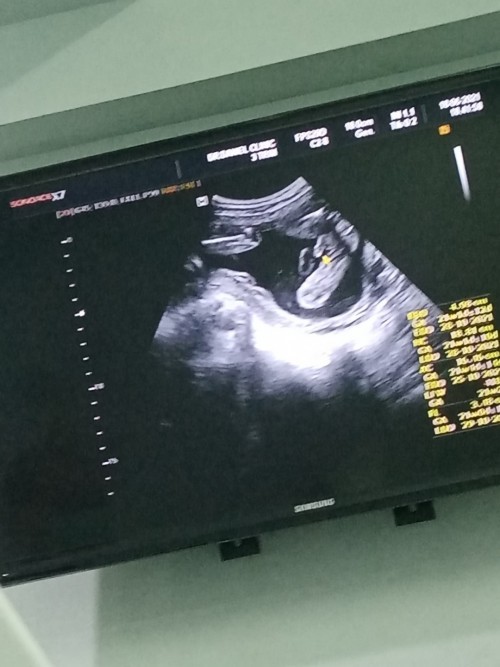

12w5dยังไม่เหนเพศเหมือนกันจ้า

ตอนนี้14วีค ได้ผู้หญิงค่ะ